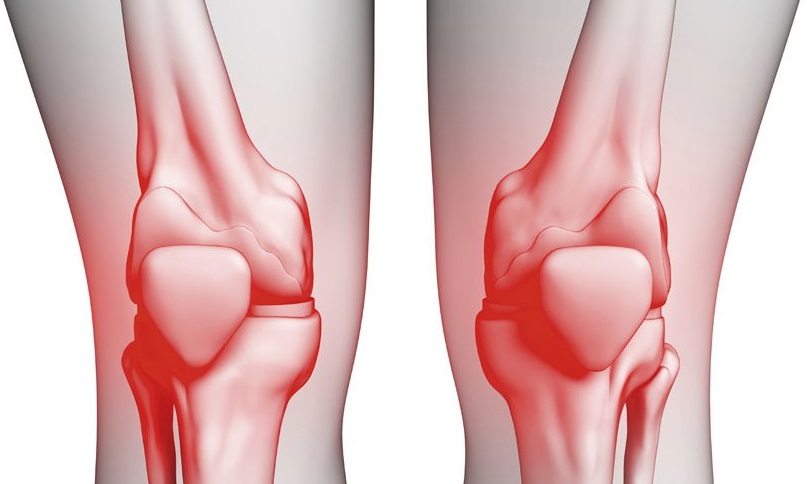

Заболевания и медицинские снимки: Жидкость в коленной чашечке